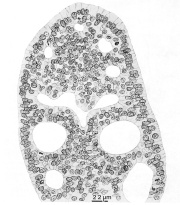

Cross section of the duodenal epithelium

Location of the micrograph

Diagram of cross sectioned eye